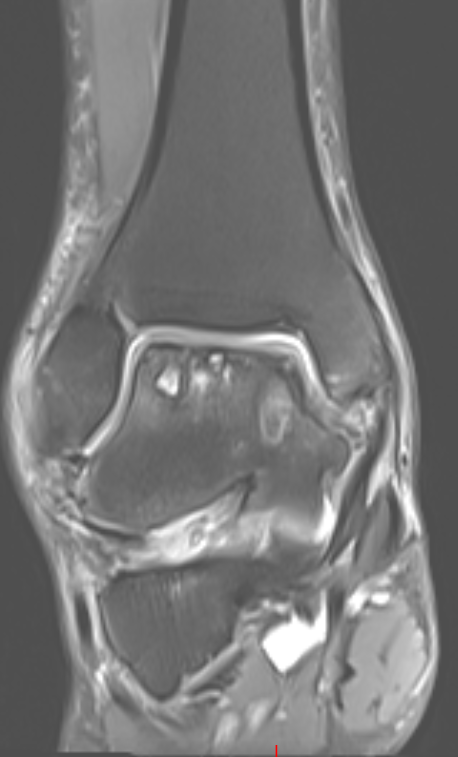

第二位是54岁的大哥,“脚脖子”痛了3年,检查发现只有部分距骨出了问题。

术前磁共振

针对这种局部病变,团队用了3D打印部分距骨置换术。

这种手术不用大动,只换病变的那部分距骨,尽量保住健康的关节组织,创伤小,术后恢复起来也能快一点。